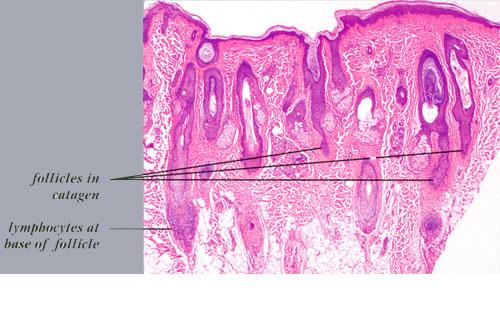

The diagnostic pathologic feature is peribulbar lymphocytic inflammation (“swarm of bees”) affecting anagen follicles or follicles in early catagen. The inflammatory assault on anagen follicles induces a premature conversion to catagen . Consequently, the number of catagen and telogen follicles found may be marked, approaching 100% . Follicles may enter a persistent phase of telogen in which the hair shaft has already been shed, manifested by the telogen germinal unit .As follicles enter catagen, the lymphocytic infiltrate may persist around the epithelial remnant of the receding follicle and also within and surrounding the collapsed follicular sheaths. Telogen hairs show little to no perifollicular inflammation.

Whiting and others have emphasized the use of follicular counts to aid in the diagnosis of AA when the characteristic peribulbar inflammation is missing, with a high percentage of catagen or telogen hairs and miniaturized hairs as a strong sign of AA .In one study, the presence of eosinophils around the bulb and within fibrous tracts was found to be a helpful diagnostic feature of AA, identifying it in 38 of 71 patients. In biopsies lacking peribulbar lymphocytic inflammation, eosinophils were found approximately 50% of the time . Some plasma cells may also be present.